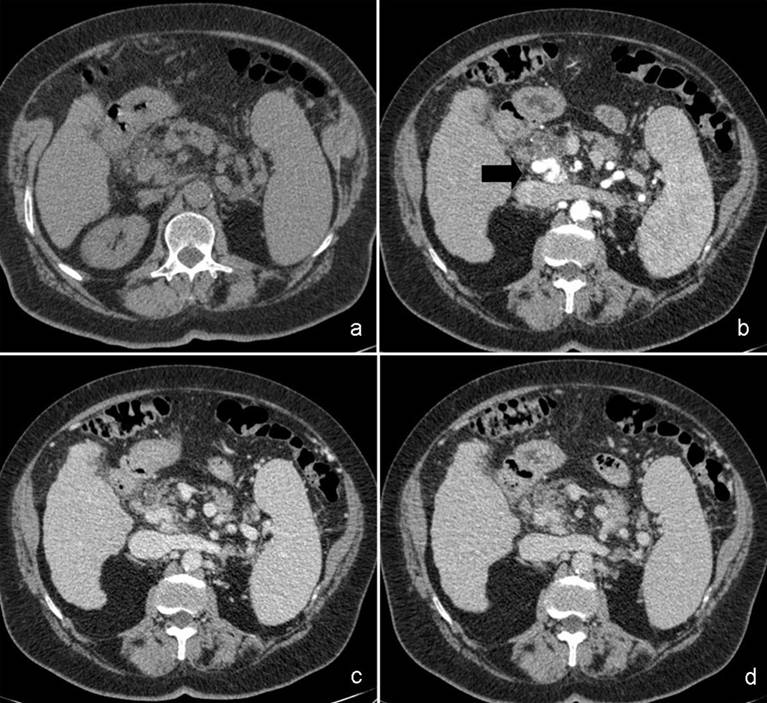

A 75-year-old female performed a quadriphasic abdominal CT examination for the characterization of a focal hepatic lesion, previously identified with a transabdominal ultrasound. Patient had a chronic HCV infection. The physical examination was substantially negative: particularly, the patient did not show any sign or symptom related to the pancreatic arteriovenous malformation or to gastrointestinal bleeding. The MDCT showed a hypervascular area of 3.5x2.5 cm in the pancreatic head, constituted of ectasic vessels (Figure 1); no calcifications were seen inside the mass. The lesion did not determine mass effect or dilation of the main pancreatic duct. During the arterial phase, there was also an early filling of the portal vein and the proximal portion of the superior mesenteric vein. Para-coronal maximum intensity projection and 3D electronic reconstructions made possible to identify the arterial afferents to the malformation (Figure 2), constituted by small aberrant branches from left gastric artery (Figure 3) and posterior inferior pancreaticoduodenal artery (Figure 4); it was also possible to identify the venous efferent drainage, constitute by the portal vein (Figure 5) and the superior mesenteric vein (Figure 6). Other MDCT findings were: presence of a cirrhotic liver with a solid 3.0x2.5 cm mass in the II segment, hyperdense in the arterial phase with washout during the portal phase, referable to hepatocellular carcinoma; an aberrant replacing right hepatic artery arising from the superior mesenteric artery; and a 1.5 cm solid hypodense lesion in the pancreatic body, with fat density and without contrast enhancement, referable to pancreatic lypomatosis.

Figure 1. Quadriphasic MDCT axial images, showing a hypervascular lesion in the arterial phase, made up of ectasic, tortuous vessels, at the pancreatic head (solid arrow in panel b). |